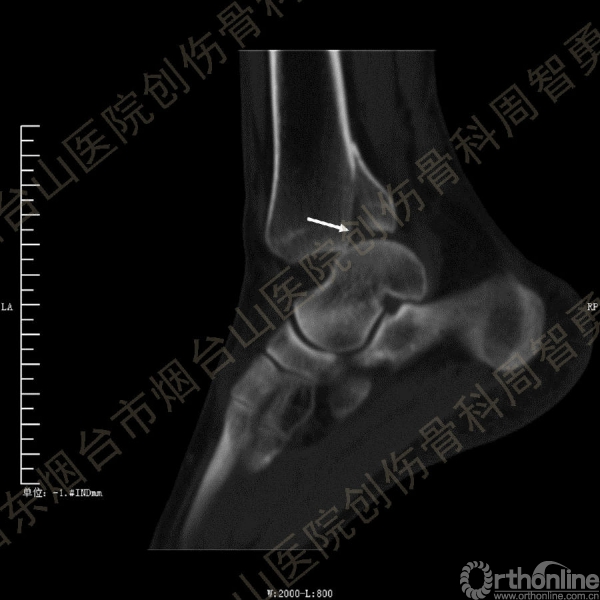

患者一般情况可,左踝关节肿胀,见皮下瘀斑,内、外、后侧有压痛,左踝关节主动运动受限,左足皮肤感觉、血供未见明显异常,左足趾各关节可主动运动。左踝关节正位X线片和CT重建示内踝内上方双层骨皮质影(图1a,c),CT示后侧骨折块分为后内侧骨折块和后外侧骨折块(图2a,b),后内侧骨折块累及内踝后丘,后丘骨折线呈冠状位(图2c),后内侧骨折块腹侧有向近端塌陷的小块骨软骨骨折块(图2d),CT也显示Chaput骨折块(图1c,2e)。

经典的后踝骨折发生于低能量旋转外力所致的踝关节骨折;标准pilon骨折见于高能量轴向暴力;而后侧pilon骨折是旋转外力和轴向暴力共同作用的结果,属于中等能量的损伤。踝关节骨折中的后踝骨折源自下胫腓后韧带的牵拉,骨折块位于后外侧,常为单一的三角形骨折块,大小从关节外片状骨折到累及胫骨远端关节面矢状径的40%(图4a)。后侧pilon骨折中的后侧骨折块较大,累及内踝后丘(三角韧带深层起点)在内的整个胫骨远端后侧,分为后内侧骨折块和后外侧骨折块,后内侧骨折块腹侧有向近端塌陷的骨软骨骨折块(图4b)。后侧pilon骨折中的内踝骨折线并不是水平位而是冠状位,可合并内踝前丘骨折。后侧pilon骨折踝关节正位X线片示特异性的内踝内上方双层骨皮质影(图1a,c)。这是由于后内侧骨折块的骨折线延伸到胫骨远端骨骺和干骺端的内侧骨皮质,其移位后的边缘成像所致。水平位CT显示后侧骨折块分为后内侧骨折块和后外侧骨折块,矢状位CT示后内侧骨折块腹侧有向近端塌陷的骨软骨骨折块。

③影像表现:踝关节正位X片显示特异性的内踝内上方双层骨皮质影

↑图 1c

图 1 术前左踝关节正侧位X线片和CT重建,箭头所示内踝内上方双层骨皮质影(a,c)